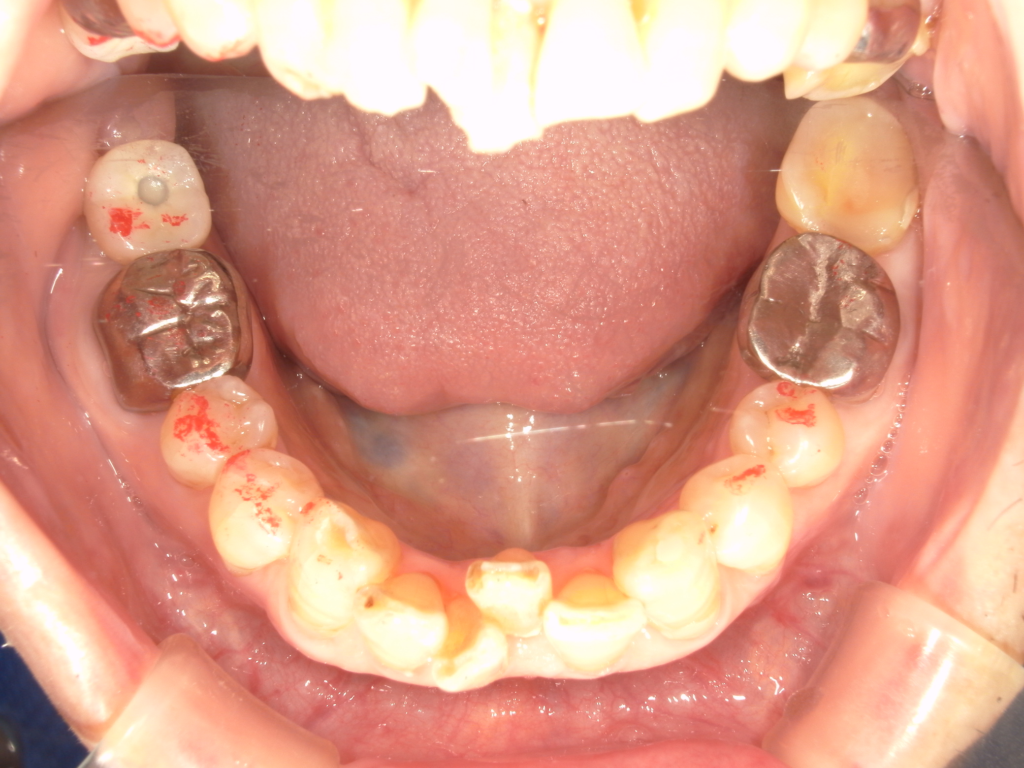

T様 60代女性 インプラント実例 #18

右下の奥歯をかめるようにしたいとのことで、インプラント治療を希望しました。2本インプラントを埋入しています。かぶせものはセラミックで作っています。治療期間は2か月半くらいです。写真の青い点はかみ合わせをチェックした点が残っています。自然にきれいに消えます。

治療前

治療後